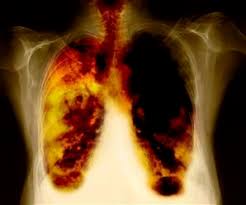

CANCER DEL PULMON

El cáncer de pulmón es uno de los cánceres más comunes en el mundo. Es la principal causa de muerte por cáncer entre los hombres y las mujeres en los Estados Unidos. El fumar cigarrillos causa la mayoría de los cánceres de pulmón. A mayor cantidad de cigarrillos diarios que fume al día y cuanto más joven se comienza a fumar, mayor será el riesgo de desarrollar un cáncer de pulmón. La exposición a altos niveles de contaminación, radiación y asbesto también puede aumentar el riesgo.

Existen muchos tipos de cáncer de pulmón. Cada uno de ellos crece y se disemina de un modo distinto y se trata de una forma diferente. El tratamiento también depende del estadio o de qué tan avanzado se encuentre. El tratamiento puede incluir quimioterapia, radiación y cirugía.